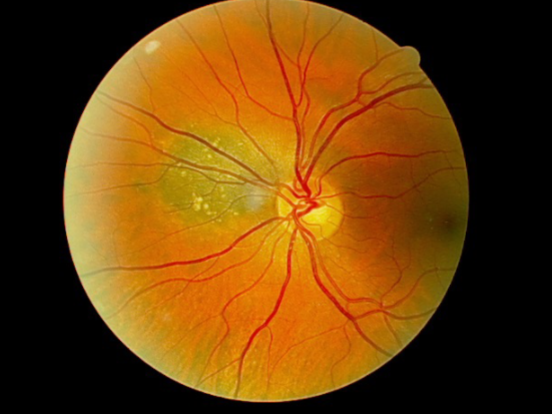

solitary choroidal hemangioma

choroidal hemangioma

choroidal hemangioma

choroidal hemangioma

choroidal hemangioma

choroidal hemangioma